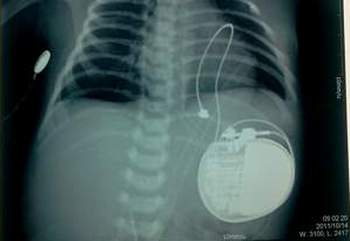

Máy tạo nhịp tim vĩnh viễn được đặt ở lồng ngực bé gái 1 ngày tuổi, con của sản phụ Thanh.

Êkíp của Trung tâm tim mạch gồm: Ths.Bs. Lê Bá Minh Du; TS.BS. Nguyễn Cửu Lợi; Ths.BS. Nguyễn Lương Tấn; BS. Dương Đăng Hoá; Ths.BS. Hoàng Văn Quý... đã chẩn đoán chị Lê Thị Tuyết Thanh có thai 35 tuần bị nhịp tim thai chậm do block nhĩ thất bẩm sinh. Phối hợp với các BS chuyên khoa sản, nhi, chị Tuyết Thanh được phẫu thuật cấp cứu lấy thai vào 20h30 ngày 13/10/2011. Trẻ sơ sinh là một bé gái nặng 2,8kg bị block nhĩ thất cấp III bẩm sinh với nhịp tim thai từ 40 đến 48 lần/phút.

Trẻ được hồi sức cho các thuốc tăng nhịp tim (isuprel), nhưng không hiệu quả nên được chuyển khẩn về phòng mổ tim thuộc Trung tâm tim mạch tiến hành mổ, đặt máy tạo nhịp cấp cứu. Lúc 0h ngày 14/10/2011, đã phẫu thuật đặt máy tạo nhịp vĩnh viễn, đưa nhịp tim của bé từ 45 lần/phút lên đến 90 lần/phút. Cuộc mổ được tiến hành trong 1h30 phút. Sau mổ trẻ được chuyển ra hồi sức tim mạch tiếp tục thở máy, trong 24h sau mổ và được theo dõi sát về mặt huyết động. Trẻ được bỏ máy thở và rút nội khí quản sau đó. Sau 4 ngày nằm phòng hồi sức, trẻ ổn định, mạch từ 90 - 120 lần/phút, trẻ bú tốt. Trẻ tiếp tục được chuyển xuống khoa ngoại lồng ngực theo dõi trong vòng 6 ngày thì được xuất viện vào ngày 24/10/2011 với tình trạng khoẻ mạnh.